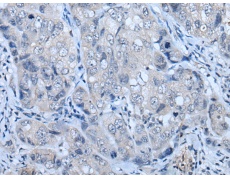

IHC positive control: |

Human breast cancer |

IHC Recommend dilution: |

20-100 |